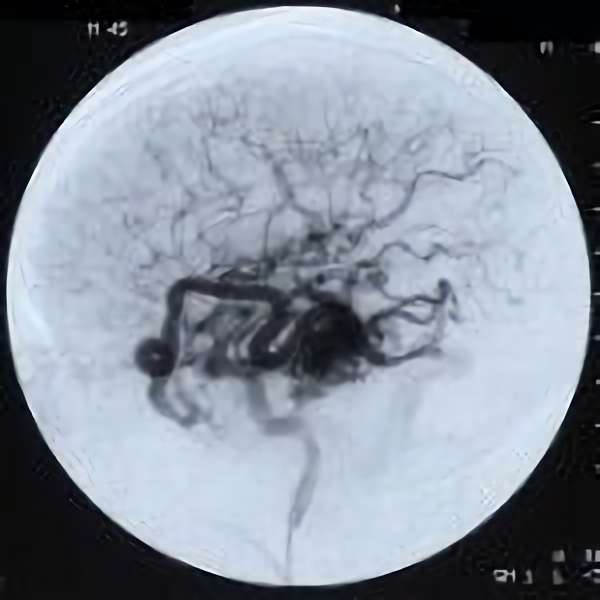

No.359 モニタリング

No.359 手術前

No.359 手術中

No.359 手術後

出血既往があり。2回の手術前血管内手術の後に、

Lateral transpeduncular approachにより再々出血予防を目的に

摘出手術を行う。完全摘出であることを確認した。

手術による合併症や後遺症なしで退院した。経過良好。